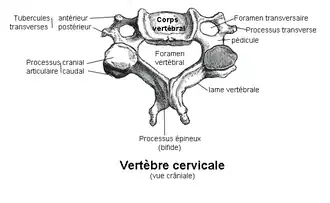

Elles présentent la structure générale des vertèbres avec un corps vertébral et un arc vertébral entourant le foramen vertébral mais avec des caractères spécifiques.

Le corps vertébral des vertèbres cervicales C3-C6 sont cubiques allongés transversalement.

Leur face supérieure est concave transversalement avec deux saillies latérales verticales : les uncus (ou apophyse semi-lunaire ou crochet ou apophyse unciforme)

Leur face inférieure est concave d'avant en arrière et convexe transversalement. Latéralement deux échancrures reçoivent les uncus de la vertèbre sous-jacente.

Les deux faces latérales reçoivent les racines antérieures des processus transverses. Leur bord antérieur se prolonge en bas formant un bec recouvrant la vertèbre sous-jacente. Leur bord postérieur se prolonge par les pédicules vertébraux. A l'arrière du pédicule s'attache la racine postérieure du processus transverse.

Les foramens (ou trous) transversaires sont formés par la face externe des pédicules, les deux racines du processus transverse et leur jonction. C'est le passage des artères vertébrales et des veines vertébrales.

La face supérieure de la jonction osseuse du processus transverse est creusé du sillon du nerf spinal pour le passage de ces derniers. Le sommet du processus porte deux tubercules : les tubercules antérieur et postérieur du processus transverse.

Les bords supérieur et inférieur des pédicules sont échancrés pour former avec les vertèbres voisines les foramens intervertébraux.

À l'arrière des pédicules les lames vertébrales se dirigent en bas, en arrière et en dedans. Elles sont plus longues que hautes. Elles portent en arrière le processus épineux court et large portant une gouttière inférieure recevant le bord supérieur du processus épineux sous-jacent. Son sommet porte deux tubercules.

À l'union des lames et des pédicules une colonne osseuse porte les processus articulaires supérieurs et inférieurs. La surface articulaire supérieure est orientée en arrière, en haut et légèrement en dehors. La surface articulaire inférieure est orientée en avant, en bas et légèrement en dedans.

Le foramen vertébral est large et triangulaire à base antérieure.